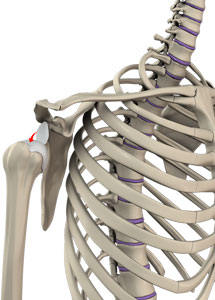

Shoulder instability is a chronic condition that causes frequent dislocations of the shoulder joint.

A dislocation occurs when the end of the humerus (the ball portion) partially or completely dislocates from the glenoid (the socket portion) of the shoulder. A partial dislocation is referred to as a subluxation whereas a complete separation is referred to as a dislocation.